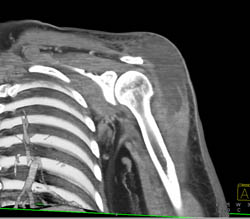

Deltoid Abscess